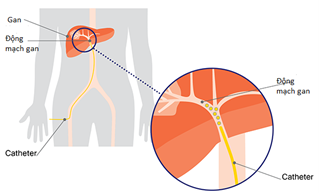

Hình 1. Mô phỏng quá trình nút mạch gan – một phương pháp ĐQCT điều trị ung thư gan

Các bác sĩ có thể sử dụng ĐQCT để đưa các thuốc hóa chất hay thuốc phóng xạ trực tiếp vào khối u cũng như các tế bào ung thư. Các bác sĩ cũng có thể tiêu diệt các tế bào ung thư và khối u bằng cách dùng sóng vô tuyến hoặc dòng điện để làm nóng, hoặc dùng các tinh thể đá để làm đông lạnh. Cùng thời điểm điều trị ung thư bằng cách phương pháp khác, các bác sĩ cũng có thể chặn đứng dòng máu nuôi khối u như một cách điều trị phối hợp để tiêu diệt khối u và các tế bào ung thư. Các nhà điện quang can thiệp cũng có thể điều trị các tác dụng phụ của các phương pháp điều trị ung thư khác như thuyên tắc mạch hay tích tụ dịch trong cơ thể bệnh nhân.